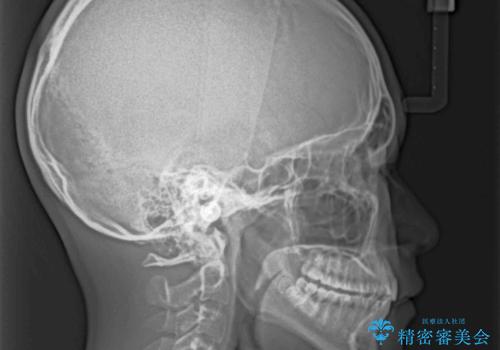

突き上げによる隙間を予防する為に、深い咬み合わせを改善するような治療計画としました。咬み合わせを改善させることはできましたが、隙間は後戻りしやすいので、通常の下顎前歯のみではなく、上顎前歯2本もワイヤーで保定を行いました。

高校生ということで、非常に短期間で治療を終えることができました。